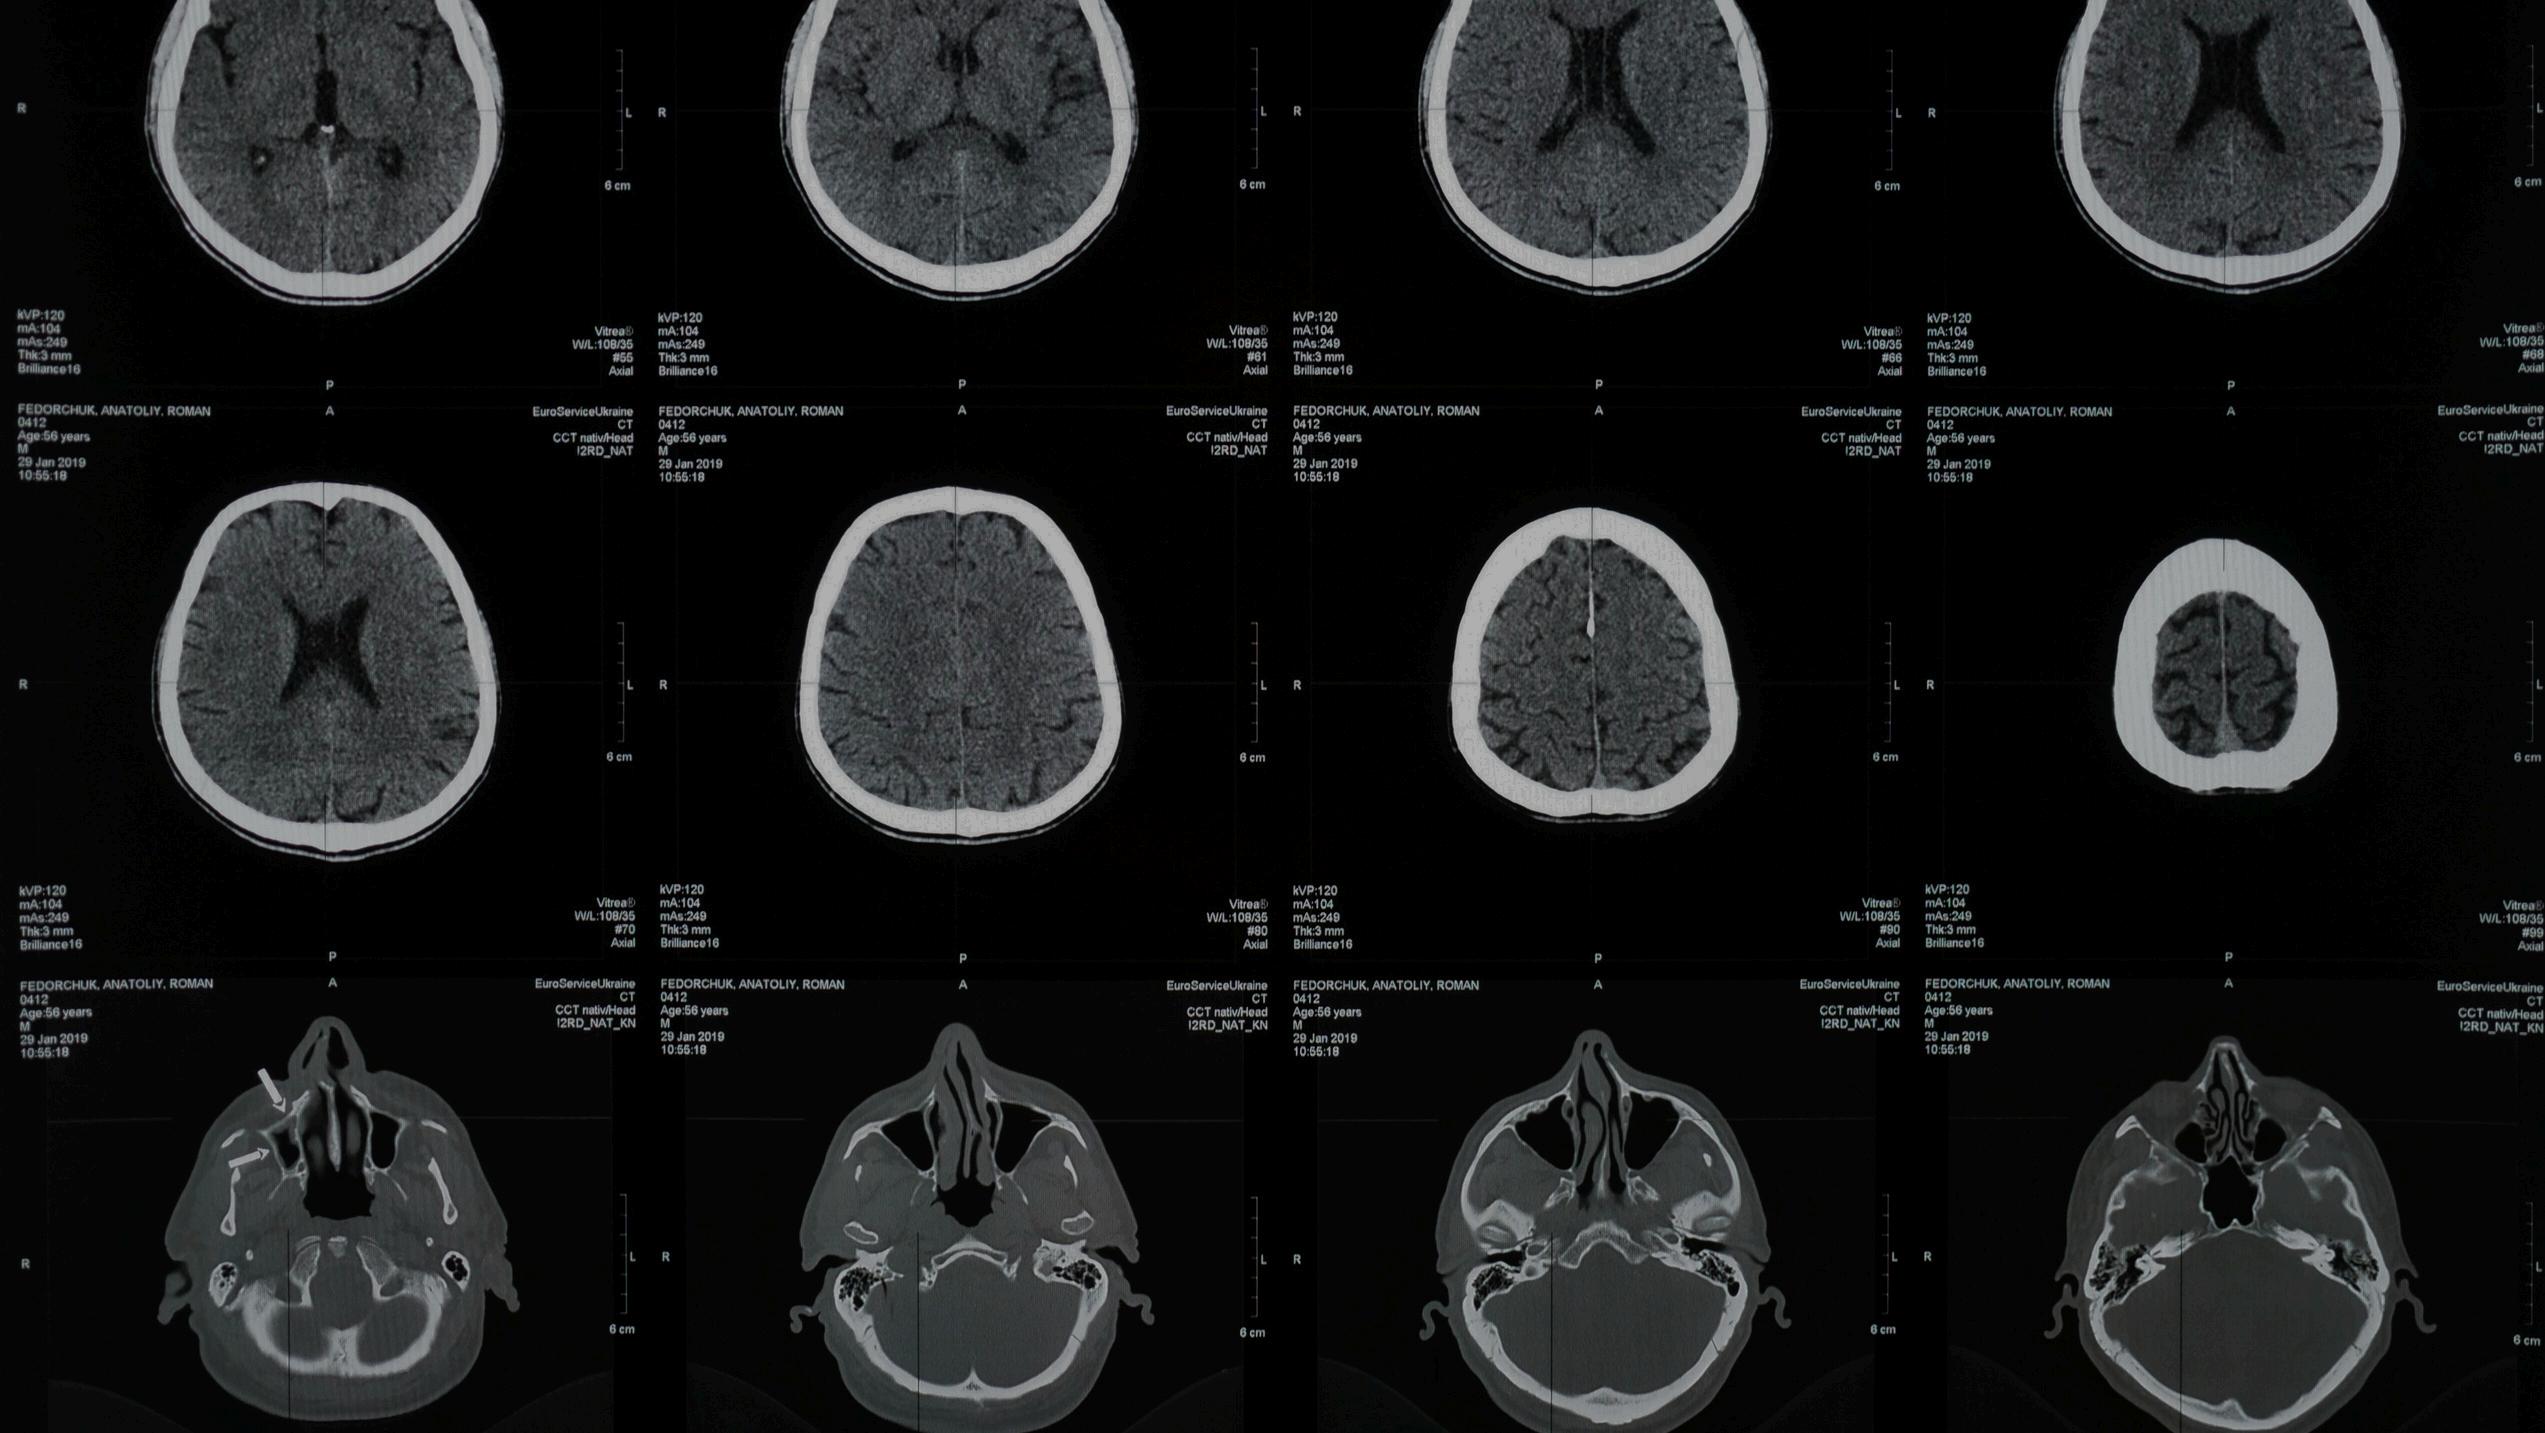

Within the complex landscapes of the human body exist anomalies that captivate and confound both medical professionals and laypeople alike This article will discuss five bizarre, perplexing syndromes that sound like storybook fantasies, delving into details such as their discovery, causes, symptoms, treatment, and more From surreal perceptual distortions to delusions that seem straight out of a horror movie, get ready to explore the captivating realms of these curious conditions.

Alice in Wonderland Syndrome

Alice in Wonderland syndrome (AIWS), also known as Todd's syndrome, is a rare neurological condition characterized by perceptual distortions that can cause individuals to perceive objec their own bodies as significa larger (macropsia) or smalle (micropsia) than they are, in phenomenon known as metamorphsia According to National Institutes of Health was first discovered in 1955 British psychiatrist Dr John He initially coined the term in Wonderland syndrome” i reference to Lewis Carroll's

"Alice's Adventures in Wonderland," due to the hallucinations experienced by the protagonist in the story. This syndrome, often associated with migraines, viral infections, and epilepsy, typically manifests during childhood and adolescence, though it can occur at any age. The exact cause of AIWS remains elusive, but it is believed to result from abnormal functioning in the brain's sensory regions. Symptoms may include visual hallucinations, time distortions, altered sense of touch, and disorientation. While the origins of the syndrome are still being investigated, treatments often focus on managing underlying conditions and may include medications to alleviate symptoms and prevent migraines.